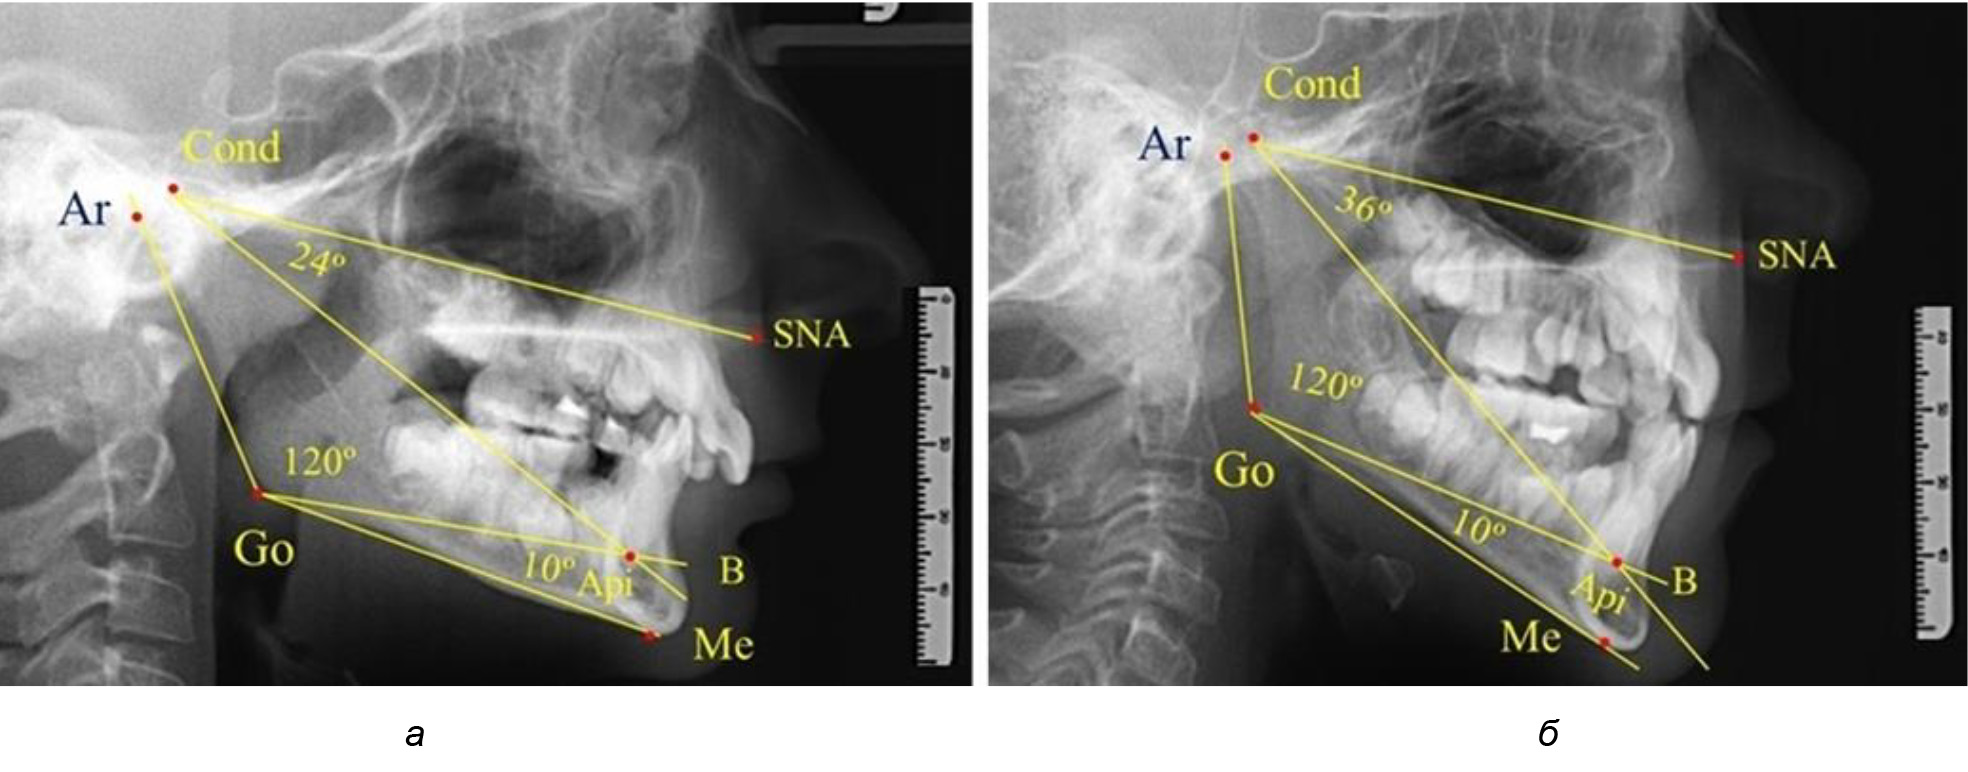

Таким образом, в периоде молочного прикуса с оптимальными окклюзионными соотношениями, несмотря на линейные размеры в вертикальном и сагиттальном направлении, которые, безусловно, меньше параметров взрослых людей, величина основного угла гнатической части лица SNA-Cond-Api соответствовала параметрам людей с полностью сформированным физиологическим прикусом постоянных зубов. Анализируя данные рентгенограмм детей в периоде сменного прикуса, отмечено, что величина основного угла гнатической части лица SNA-Cond-Api, так же как в молочном и постоянном прикусе, в норме составляла от 28 до 32°. В то же время угол нижней челюсти и его составляющие отличались вариабельностью параметров при различных показателях нижнечелюстного угла. Достоверных различий угла гнатической части после смены нижних медиальных резцов и прорезывания первых постоянных моляров (4 ребенка) не было; происходил очередной этап подъема высоты прикуса и увеличение линейных размеров костей гнатической части, однако угловые параметры были относительно стабильны. После смены всех резцов и замены первых молочных моляров первыми премолярами (6 человек) увеличивались линейные размеры при сохранившихся угловых показателях гнатической части лица (рис. 5).

Рис. 5. Варианты ТРГ после прорезывания ППМ и нижних резцов (а), всех резцов и первых премоляров (б)

Таким образом, в период сменного прикуса с оптимальными окклюзионными соотношениями, несмотря на увеличение линейных размеров в вертикальном и сагиттальном направлении, по сравнению с прикусом молочных зубов, величина основного угла гнатической части лица SNA-Cond-Api соответствовала показателям как постоянного, так и молочного прикуса с физиологическими окклюзионными соотношениями.